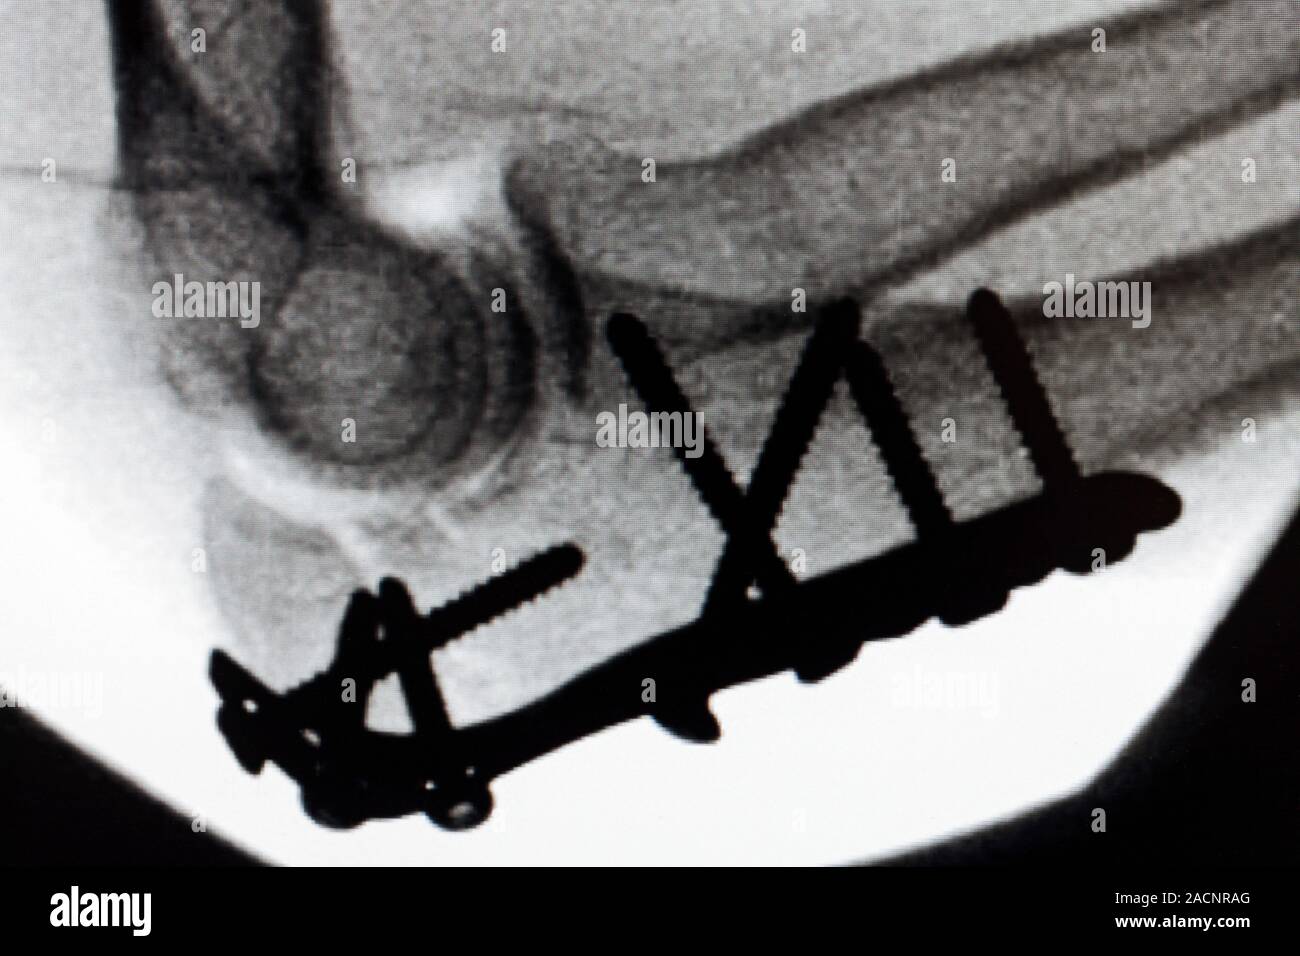

From www.freepik.com

Premium Photo Xray of an elbow showing the plate and screws with Removing Plate And Screws From Elbow for planned partial removal of hardware such as plates, nails, screws or as a bail out. the plate fits on the surface of a fractured bone and screws are placed through the holes in the plate to hold the plate to the bone. Cover bone and tissue in packs. orthopaedic hardware (plates, screws, nails and other pieces. Removing Plate And Screws From Elbow.